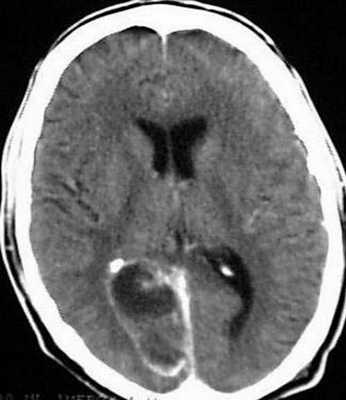

Точность диагностирования с помощью КТ головного мозга зависит от стадии формирования абсцесса. На ранних стадиях заболевания диагностика затруднена. На этапе раннего энцефалита (1-3 сутки) КТ определяет зону сниженной плотности неправильной формы. Введенное контрастное вещество накапливается неравномерно, преимущественно периферических отделах очага, реже в центре.

На более поздних этапах энцефалита контуры очага приобретают ровные округлые очертания. Контрастное вещество распределяется равномерно, по всей периферии очага; плотность центральной зоны очага при этом не меняется. Однако на повторной КТ (через 30-40 минут) определяется диффузия контраста в центр капсулы, а также наличие его и в периферической зоне, что не характерно для злокачественных новообразований.

Инкапсулированный абсцесс мозга на КТ имеет вид округлого объемного образования с четкими ровными контурами повышенной плотности (фиброзная капсула). В центре капсулы зона пониженной плотности (гной), по периферии видна зона отека. Введенное контрастное вещество накапливается в виде кольца (по контуру фиброзной капсулы) с небольшой прилежащей зоной глиоза.

На повторной КТ (через 30-40 минут) контрастное вещество не определяется. При исследовании результатов компьютерной томографии следует учесть, что противовоспалительные препараты (глюкокортикостероиды, салицилаты) в значительной степени влияют на скопление контраста в энцефалитическом очаге.